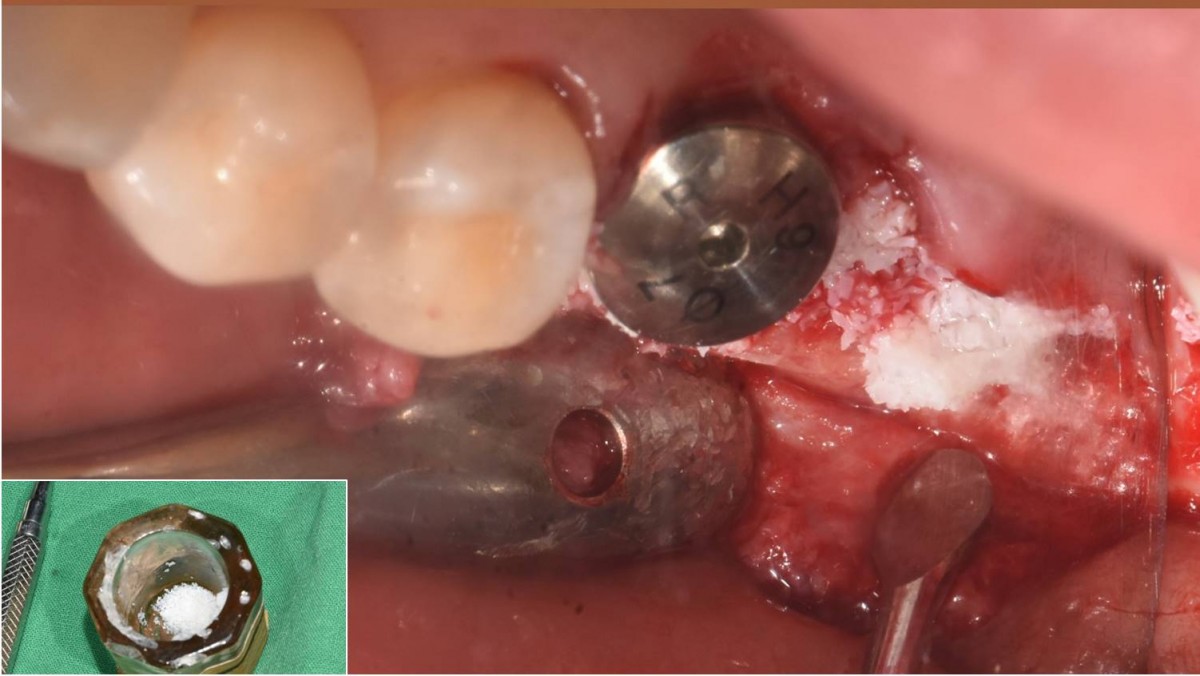

A 55-year-old female patient had

bilateral problems in both jaws.

It was decided to proceed with implant-supported restoration in the left molar part first.

She had been taking hypertension medication for a long time.